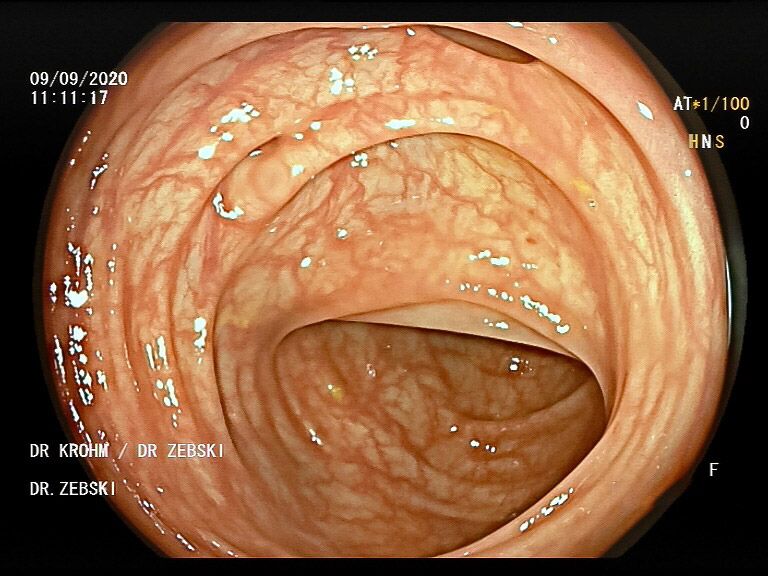

Die Darmspiegelung ist der uneingeschränkte Goldstandard für die Diagnostik und Vorsorge sämtlicher Erkrankungen des Dickdarms und des untersten Dünndarms. Die hochauflösende Bildqualität (High Definition) unserer modernen Videokoloskope ermöglicht eine zuverlässige Einordnung nahezu sämtlicher entzündlicher oder geschwulstiger Veränderungen der Dickdarmschleimhaut.

Die Darmspiegelung hilft, dass Darmkrebs gar nicht erst entstehen kann. Denn während der Untersuchung werden auch Polypen entfernt, aus denen sich der Darmkrebs in der Regel entwickelt. Von allen Maßnahmen zur Früherkennung dieser Polypen besitzt die Koloskopie die höchste Empfindlichkeit. Sie weist kleinste Polypen, aber auch Darmkrebs nach, der noch keinerlei Symptome macht. Die Abtragung dieser Polypen erfolgt direkt, wenn sie entdeckt werden. Das geschieht völlig schmerzfrei. Durch die Abtragung der Polypen kann die Entstehung von Darmkrebs effektiv verhindert und die krebsbedingte Sterblichkeit gesenkt werden.